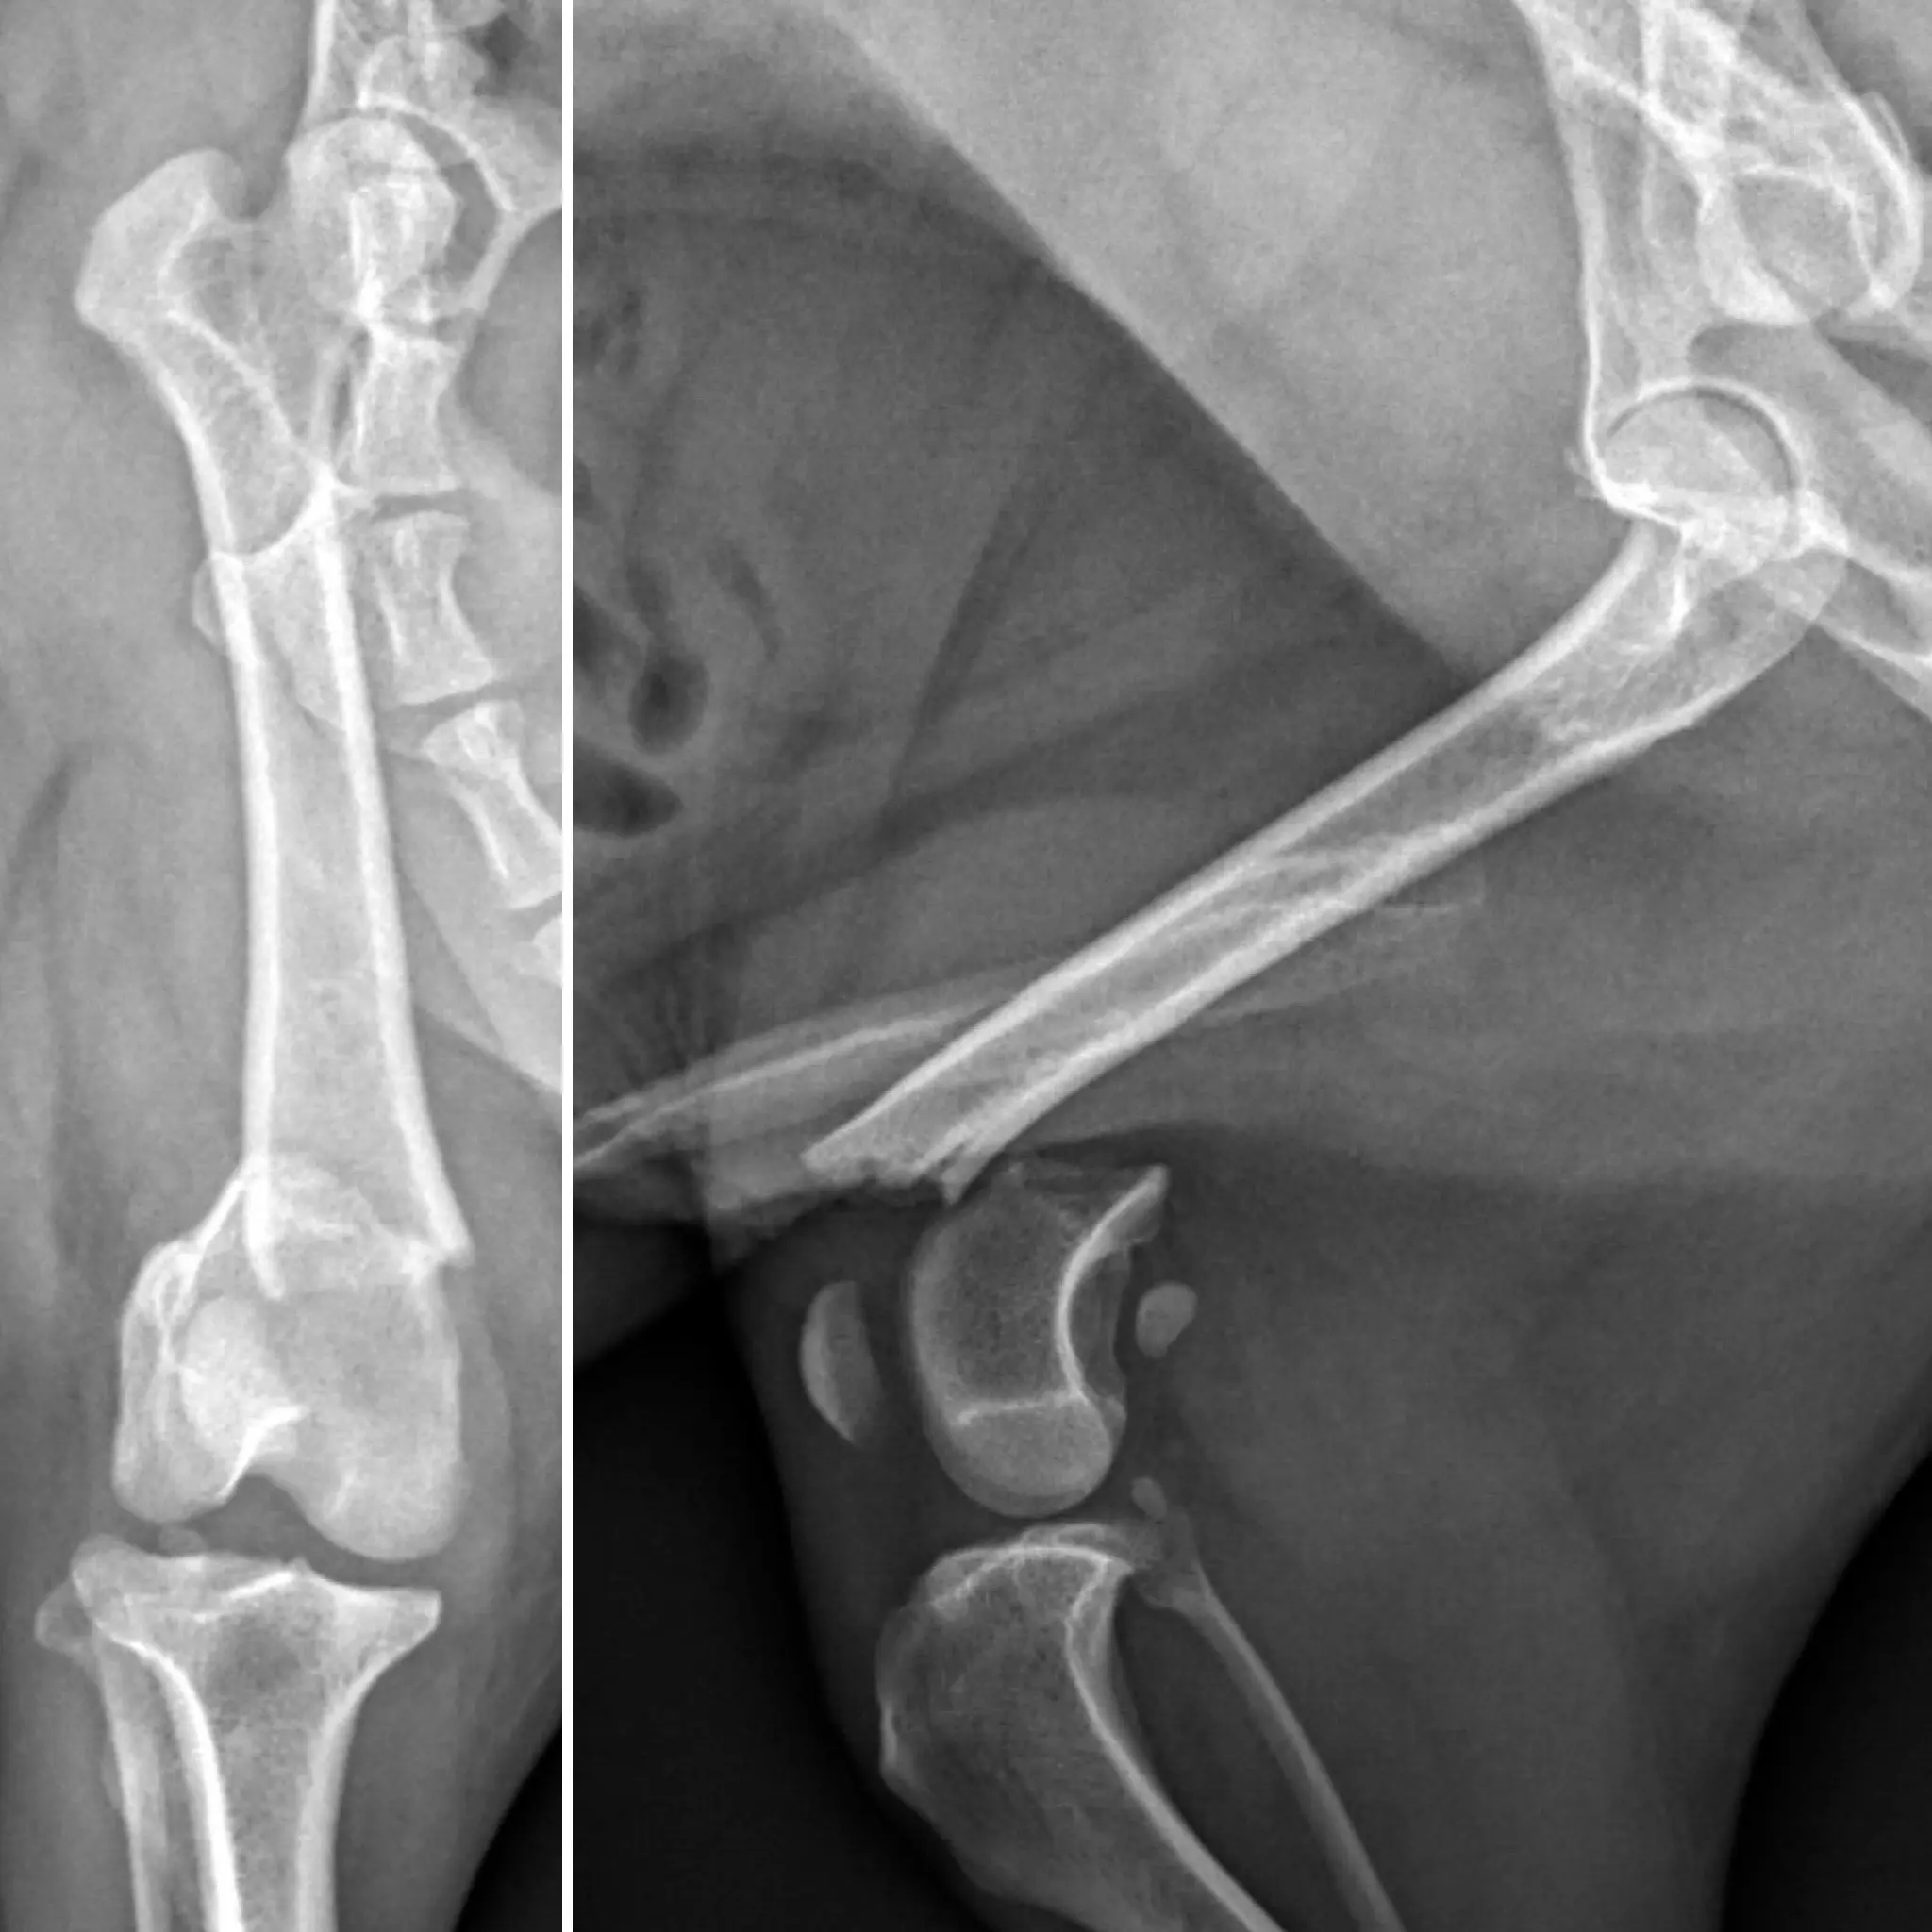

Para obtener un diagnóstico preciso, procedimos a realizar un protocolo diagnóstico completo, que incluyó un estudio radiológico. Gracias a las imágenes pudimos confirmar la causa de su cojera: Pitu presentaba una fractura metafisaria distal supracondilar del fémur derecho.

Realizamos un estudio detallado de la fractura descrita y diseñamos un plan quirúrgico mediante la utilización de un software específico. Este paso nos permite optimizar la colocación de los implantes y por tanto los resultados.